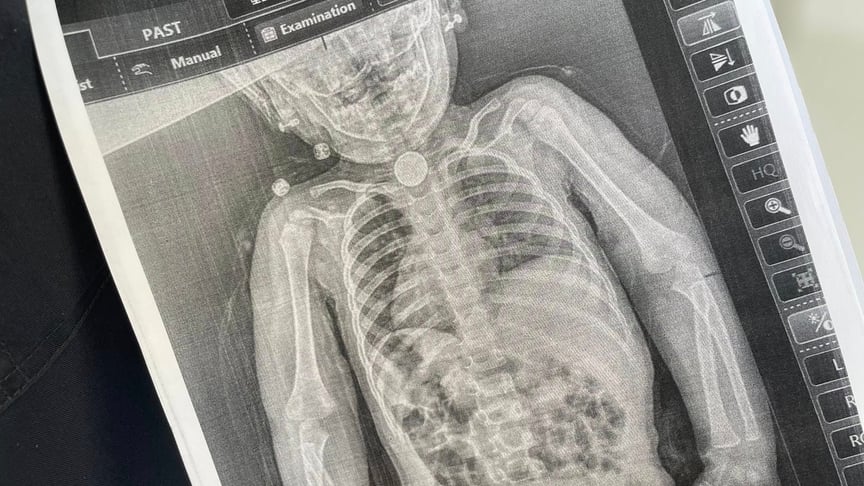

У перші дні весни в дитини з’явилися нові небезпечні симптоми: блювання, відмова від їжі, покашлювання та свистяче дихання, яке було чути навіть на відстані. Батьки знову повезли дочку до лікарні та наполягли на додатковому обстеженні. Дівчинці зробили рентген, який чітко показав стороннє тіло у стравоході.

Уже під час ендоскопічного обстеження точно встановили, що ж це було. У ділянці першого фізіологічного звуження стравоходу міцно застрягла кругла літієва батарейка діаметром 2,5 сантиметра. Навколо неї сформувалися набряк та гіпергрануляції слизової оболонки — ознаки тривалого ушкодження тканин.